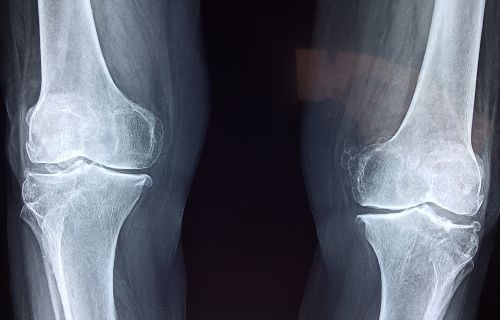

골다공증은 뼈 손상과 약화로 인해 발생하는 심각한 건강 문제 중 하나입니다. 특히 고령자에게 더욱 많은 위험을 안겨, 골절 및 기타 심각한 문제로 이어질 수 있습니다. 그러나 건강한 뼈를 유지하고 골다공증을 예방하기 위해서는 적절한 운동이 필수입니다. 이번 글에서는 골다공증에 좋은 운동을 알아보고, 어떻게 뼈 건강을 유지할 수 있는지 알아보겠습니다.

골다공증은 뼈 밀도 감소로 인해 발생하는데, 운동은 뼈 밀도를 증가시키고 유지하는 데 도움이 됩니다.

근력 운동은 근육을 강화하고 밸런스를 향상하며, 이는 골다공증으로 인한 골절 위험을 줄여줍니다.